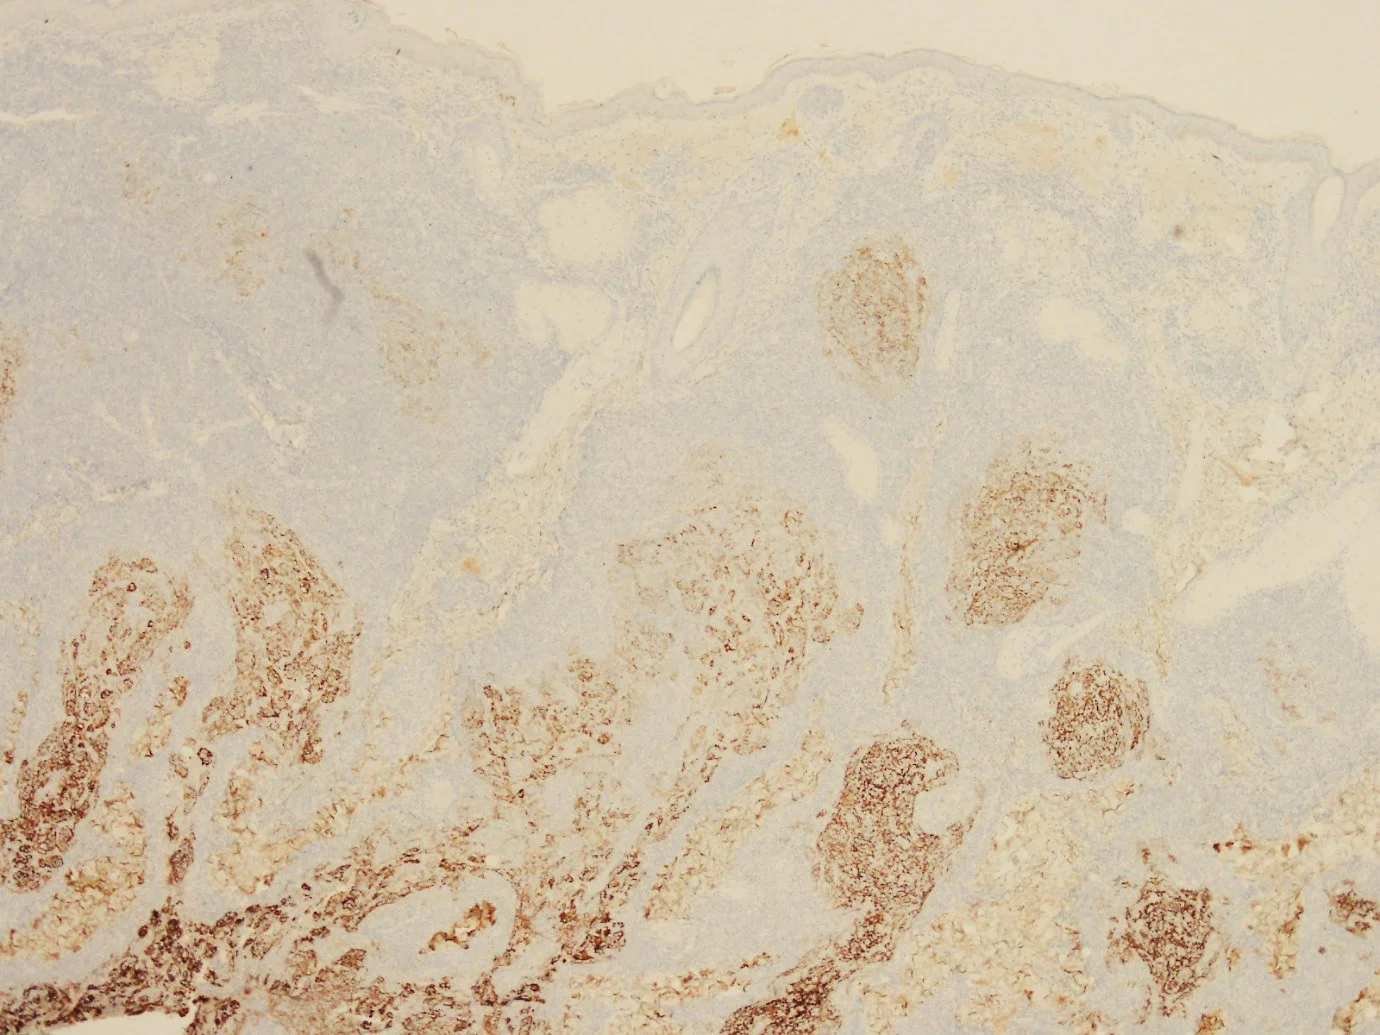

CD20

CD21

D10

BCL2

BCL6

CD79a